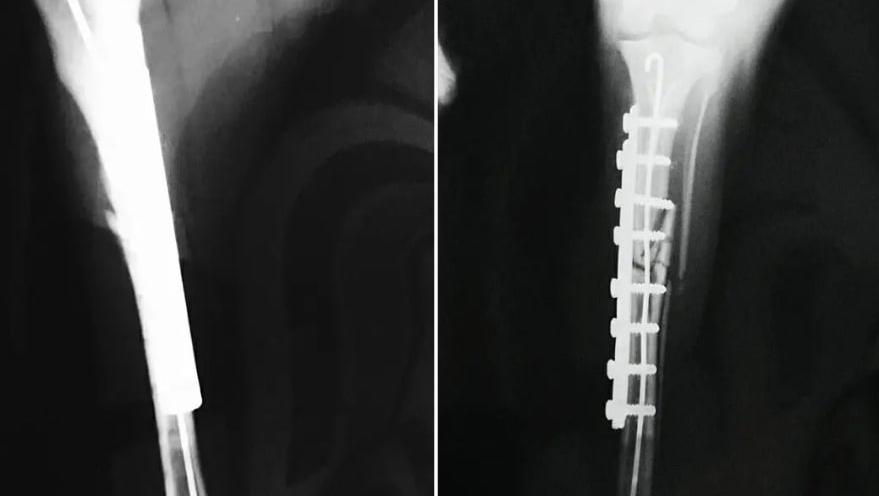

Ветеринарная клиника Ветдопомога — это место, где профессиональная медицина сочетается с искренней эмпатией к каждому четвероногому пациенту. Команда клиники воспринимает свою работу не просто как оказание услуг, а как миссию — быть рядом с владельцами в самые ответственные моменты, обеспечивая животным долгую и здоровую жизнь. Здесь одинаково заботливо относятся как к домашним питомцам, так и к бездомным животным, ведь в основе ценностей учреждения лежит убеждение, что каждая жизнь заслуживает спасения и заботы. Клиника предлагает полный спектр помощи — от плановых осмотров, вакцинации и чипирования до сложных хирургических вмешательств и комплексного лечения внутренних болезней.

Благодаря современному оборудованию и высоким стандартам стерильности, врачи проводят точную диагностику и эффективную терапию, всегда оставаясь на связи с владельцами для предоставления бесплатных консультаций и советов по правильному содержанию животных. Специалисты учреждения не боятся сложных случаев, применяя свой многолетний опыт, чтобы даже в самых трудных ситуациях вернуть хвостикам радость жизни, а их хозяевам — спокойствие. Каждый визит в «Ветдопомогу» — это история о доверии, где пациент ощущает тепло человеческих рук, а владелец получает профессиональную поддержку и уверенность в качестве лечения своего друга.